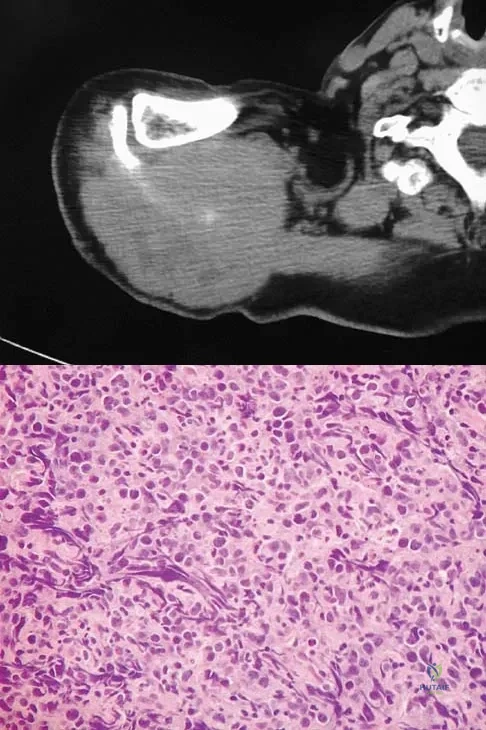

A 60-year-old woman has a mass in the right scapula. Figures 25a and 25b show a CT scan and a biopsy specimen. The cells are lymphocyte common antigen positive, Ewing's specific antigen (CD99) negative, and keratin negative. What is the next step in management?